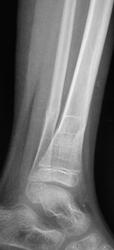

Пол пациента: Женский пол Тип патологии: Травма Область исследования: Скелетно-мышечная система Методы исследования: Rg Снят гипс. Пациент направлен на «контрольные» снимки. Какие мнения будут уважаемые коллеги? https://radiomed.ru/sites/default/files/styles/case_slider_image/public/user/12/2.p8260008.jpg?itok=6w6bzjZb https://radiomed.ru/sites/default/files/styles/case_slider_image/public/user/12/3.p8260006.jpg?itok=o220V7Pk https://radiomed.ru/sites/default/files/styles/case_slider_image/public/user/12/4.p8260007.jpg?itok=JhfzL2sT ID:15021 Вс, 28/08/2011 - 21:04 #1 Vega Не на сайте Был на сайте: 1 день 3 часа назад Зарегистрирован: 22.01.2009 - 19:16 Публикации: 1087 Смещение в вальгус не очень благоприятно, но в данном возрасте допустимо. Не спешить только с полной нагрузкой. Вс, 28/08/2011 - 21:23 #2 Катенёв Валенти... Не на сайте Был на сайте: 7 лет 3 недели назад Зарегистрирован: 22.03.2008 - 22:15 Публикации: 54876 Спасибо Вега! Пнд, 29/08/2011 - 12:29 #3 гаур моника Не на сайте Был на сайте: 14 лет 3 месяцев назад Зарегистрирован: 07.07.2011 - 12:17 Публикации: 27 была травма?????? есле после репозиции то картина хорошая... Пнд, 29/08/2011 - 14:08 #4 Катенёв Валенти... Не на сайте Был на сайте: 7 лет 3 недели назад Зарегистрирован: 22.03.2008 - 22:15 Публикации: 54876 гаур моника wrote: была травма?????? есле после репозиции то картина хорошая... Травма была, репозицию не делали, загипсовали.... Пнд, 29/08/2011 - 14:12 #5 krok Не на сайте Был на сайте: 13 лет 4 месяцев назад Зарегистрирован: 04.08.2011 - 18:13 Публикации: 13 Уважаемый Валентин Львович! Сколько лет юной прелестнице? Геннадий. Пнд, 29/08/2011 - 14:13 #6 Катенёв Валенти... Не на сайте Был на сайте: 7 лет 3 недели назад Зарегистрирован: 22.03.2008 - 22:15 Публикации: 54876 В районе 10-12. Пнд, 29/08/2011 - 14:14 #7 krok Не на сайте Был на сайте: 13 лет 4 месяцев назад Зарегистрирован: 04.08.2011 - 18:13 Публикации: 13 Благодарствую! Геннадий.

Смещение в вальгус не очень благоприятно, но в данном возрасте допустимо. Не спешить только с полной нагрузкой.

была травма?????? есле после репозиции то картина хорошая...

Травма была, репозицию не делали, загипсовали....

В районе 10-12.